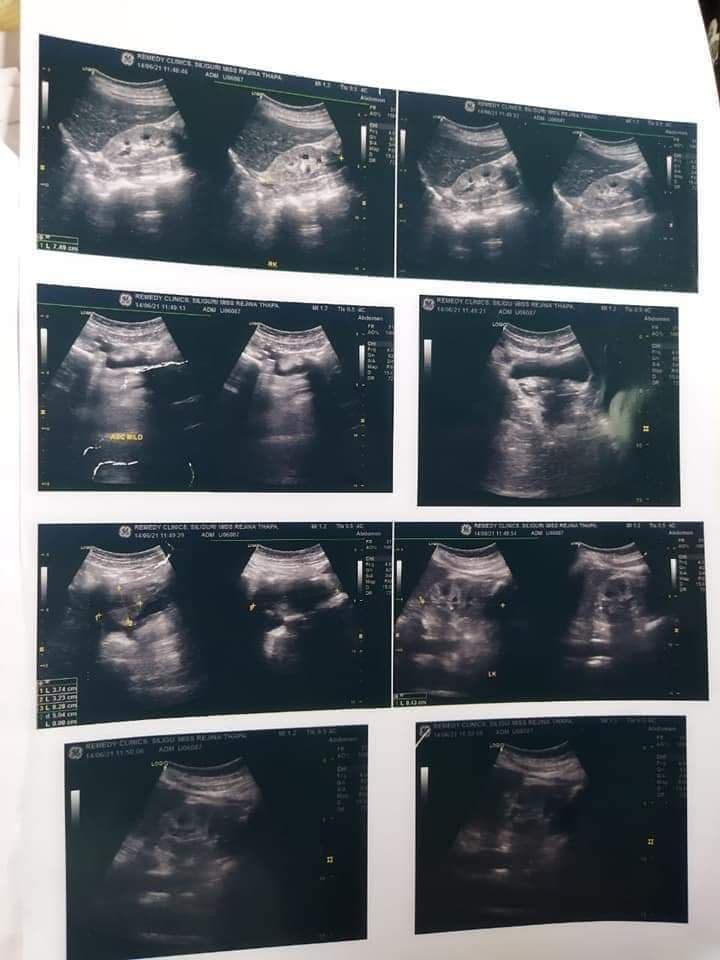

२४ वर्षीया रजनी थापाको किड्नीले काम गर्न नसक्ने भई किड्नी प्रत्यारोपण गर्नुपर्ने अवस्था सिर्जना भएको सुनेपछि उनको सहयोगका लागि मुख्यमन्त्री प्रेमसिंह तामाङले तत्काल सहयोग प्रदान गर्दै दिल्लीमा लगेर उपचार गराउने आफ्नो आधिकारिक फेसबुक पेजमा उल्लेख गरेका छन् । पश्चिम पाण्डामको रालोङ निवासी देउकुमारी थापाकी छोरी रजनी थापाको किडनीले काम गर्न छोड़ेको र छिटोभन्दा छिटो किडनी प्रत्यारोपण गर्नुपर्ने अवस्था आइपरेको आफूले विभिन्न सामाजिक सञ्जालबाट थाहा पाएपछि तत्काल पीडित परिवारसँग कुराकानी गरेको मुख्यमन्त्रीले बताएका छन् ।